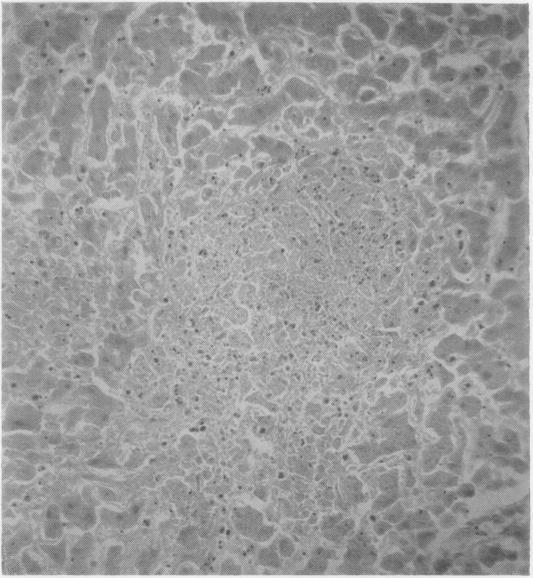

Leukaemoid reactions in disseminated tuberculosis.

J Clin Pathol. 1959 Jul;12(4):307-11. doi: 10.1136/jcp.12.4.307.